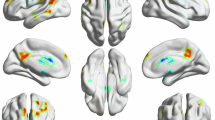

Corresponding ICA images were independently selected from the two groups according to the templates presented by GIFT. One-sample t-test result of DMN from HA and HR are shown in Fig. 1. The DMN was separated into the posterior and anterior parts. The DMN components’ thresholds were at a level of significance p < 0.05, FDR corrected with a minimal cluster size of 20. As a result, regions selected in this study match well with classical DMN regions.

We used age and methadone dosage as covariates for the group comparison and the difference in results is shown in Table 2 and Fig. 2. The left inferior temporal gyrus and right superior occipital gyrus associated with DMN showed a decrease in functional connectivity in the HR group compared with the HA group. The left precuneus and right middle cingulum show increased functional connectivity.